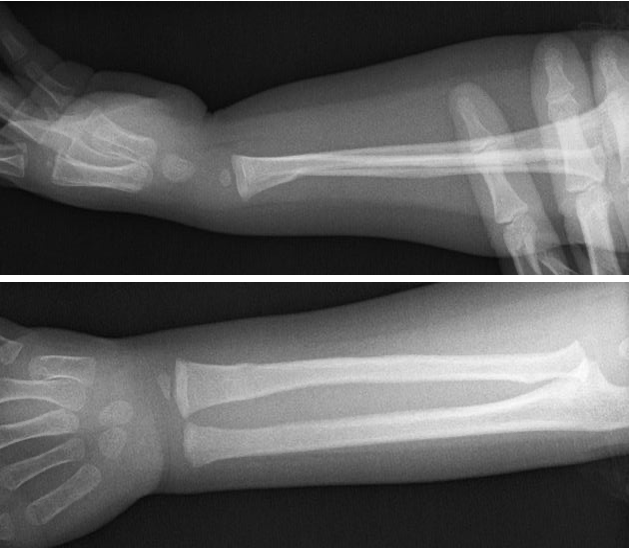

Greenstick Fracture

comprises a bend in the bone on one side and a visible break in the bone cortex on the other side, which is incomplete

due to the pliable nature of bones in children, complete fractures are less common

TORUS/BUCKLE FRACTURE

referred to as a circumferential buckle fracture, commonly of the distal radial metaphysis. No distinct fracture line, but subtle deformity of buckle of the cortex may be evident. torus = protuberance in latin